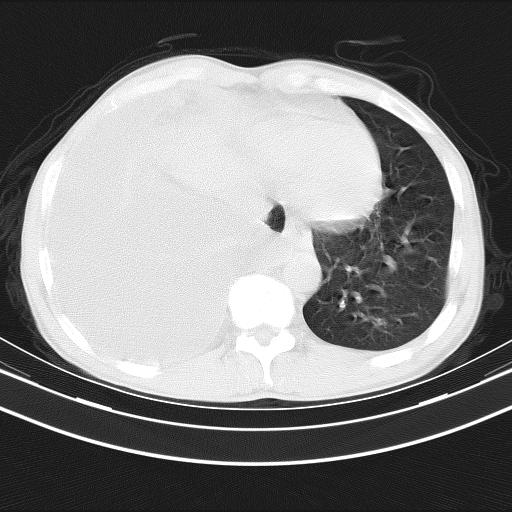

男性,44岁,结核病史多年。现胸闷气短,咳嗽,偶咳血。

右侧胸腔积液

右肺下叶不张

双肺多发结节影最分空洞形成考虑占位不除外结核

双肺陈旧性病变

1、右侧大量胸腔积液伴右肺压缩性膨胀不全,建议抽液治疗后复查 2、两肺继发性tb伴空洞形成。

1)两肺继发性肺结核伴空洞形成,左肺多发性结核球。2)右侧大量胸腔积液伴右肺部分膨胀不全。3)纵隔淋巴结肿大。